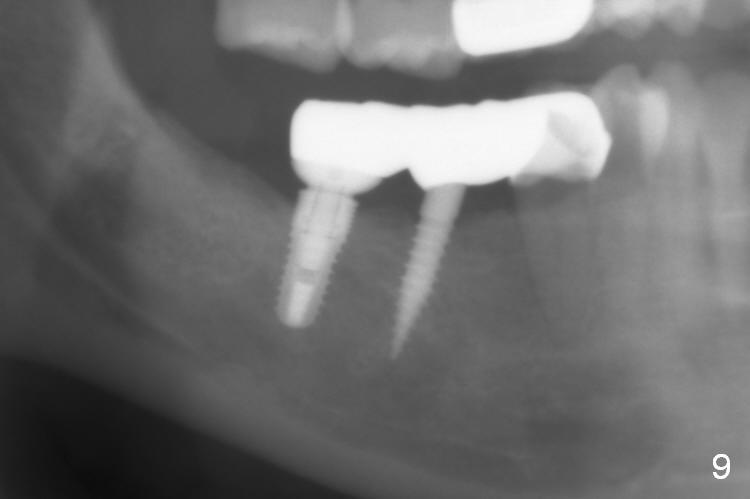

The patient returns for final restoration 3 months postop; bone resorption around the 1-piece implant is minimal (Fig.7).  The definitive restoration is also splinted.  The latter is further justified when the implant at #30 is found to be distal prior to cementation (Fig.8 *).  It appears that implant spacing at the root level is more critical than parallelism, as compared to Fig.7.  Let us improve this aspect.  Bone loss around the implants remains minimal 7 months post cementation (Fig.9).  It is the same 1 year 8 months post cementation (Fig.10), as compared to a cantilever FPD on the other side (Fig.11).  The bone density around the implants at #30 and 31 increases 2 year 8 months post cementation (Fig.12).